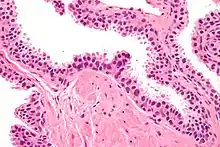

| Micrograph showing high-grade prostatic intraepithelial neoplasia. H&E stain. | |

Its cytologic features are that of prostatic adenocarcinoma:

- presence of nucleoli,

- increased nuclear-to-cytoplasmic ratio and,

- increased nuclear size.

Microscopically, PIN is a collection of irregular, atypical epithelial cells. The architecture of the glands and ducts remains normal. The epithelial cells proliferate and crowding results in a pseudo-multilayer appearance. They remain fully contained within a prostate acinus (the berry-shaped termination of a gland, where the secretion is produced) or duct. The latter can be demonstrated with special staining techniques (immunohistochemistry for cytokeratins) to identify the basal cells forming the supporting layer of the acinus. In prostate cancer, the abnormal cells spread beyond the boundaries of the acinus and form clusters without basal cells. In HGPIN, the basal cell layer is disrupted but present. PIN is primarily found in the peripheral zone of the prostate (75-80%), rarely in the transition zone (10-15%) and very rarely in the central zone (5%), a distribution that parallels the zonal distribution for prostate carcinoma.[7]

Several architectural variants of PIN have been described, and many cases have multiple patterns. The main ones are tufting, micropapillary, cribriform, and flat. Although these different appearances may cause confusion with other conditions, they have not been found to be of clinical importance. Rarer types are signet-ring-cell, small-cell-neuroendocrine, mucinous, foamy, inverted, and with squamous differentiation.[3]